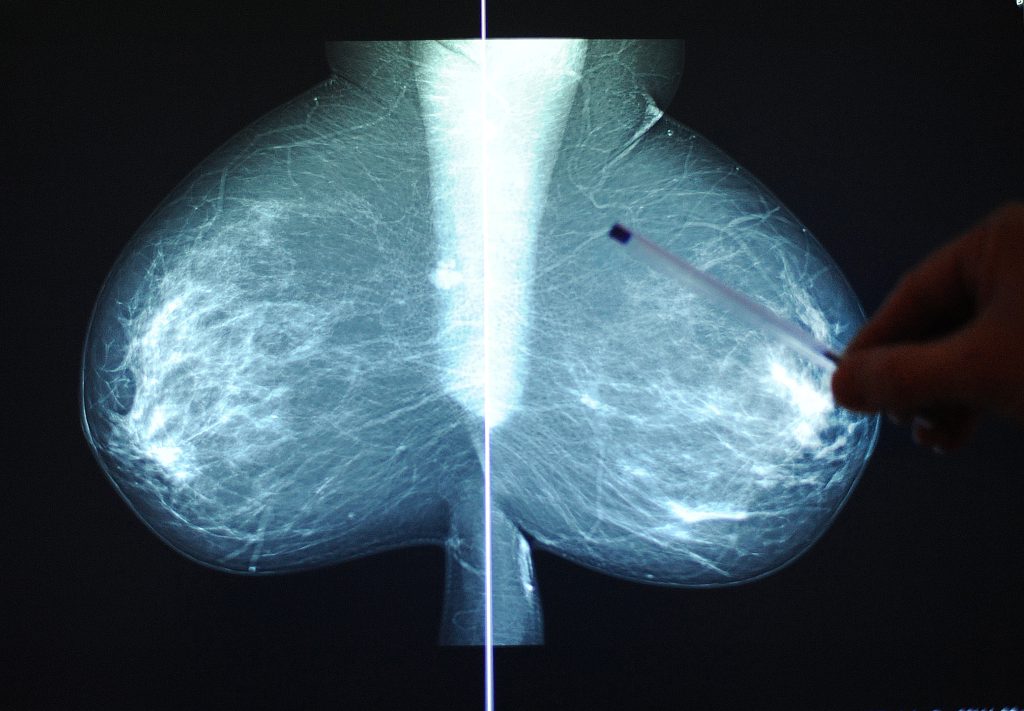

Frauen seien auch nicht genügend über die Krebs-Risikofaktoren Tabak, Alkohol, Adipositas (Fettleibigkeit) und Infektionen aufgeklärt. Zum Beispiel hätten 2019 in Grossbritannien nur 19 Prozent der Frauen, die eine Mammografie für Brustkrebserkennung durchführen liessen, gewusst, dass Alkohol einer der grössten Risikofaktoren für Brustkrebs ist.